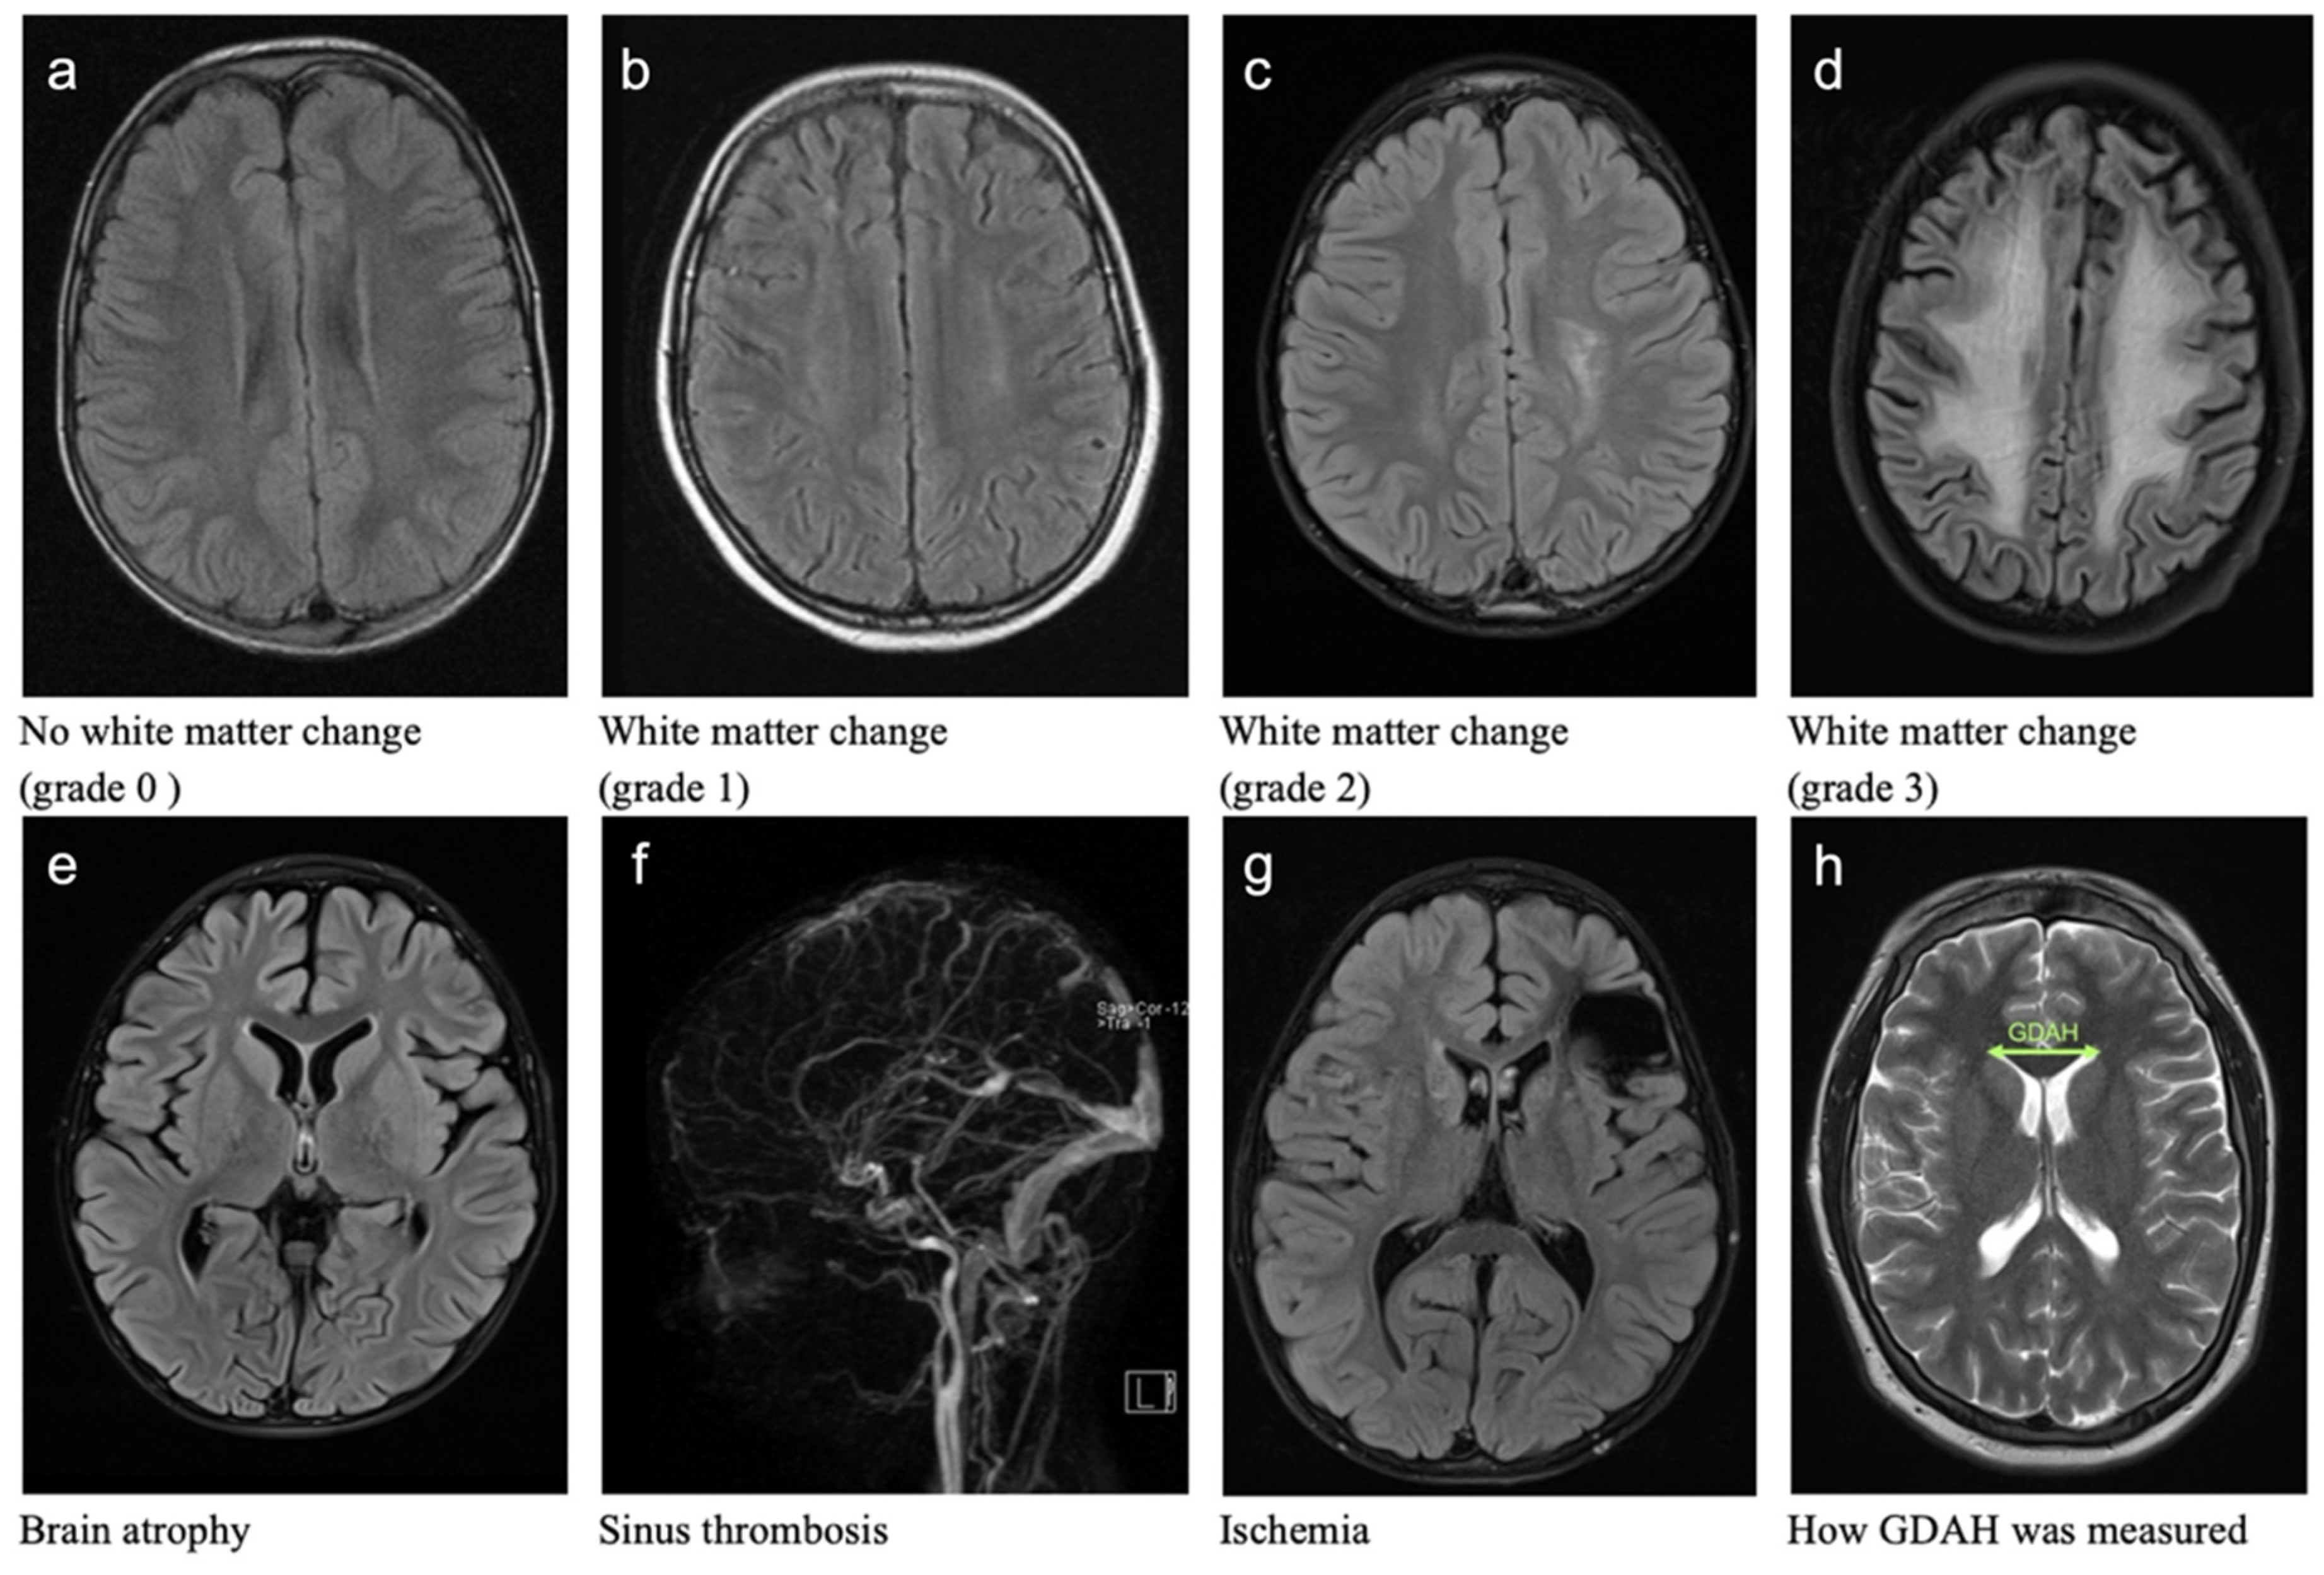

3.1.2. White Matter Changes (WMC)

3.1.3. Sinus Vein Thrombosis (ST)

3.1.4. Brain Atrophy (BA)

3.1.5. Cerebral Ischemia

3.1.6. Ventricular Width (GDAH)